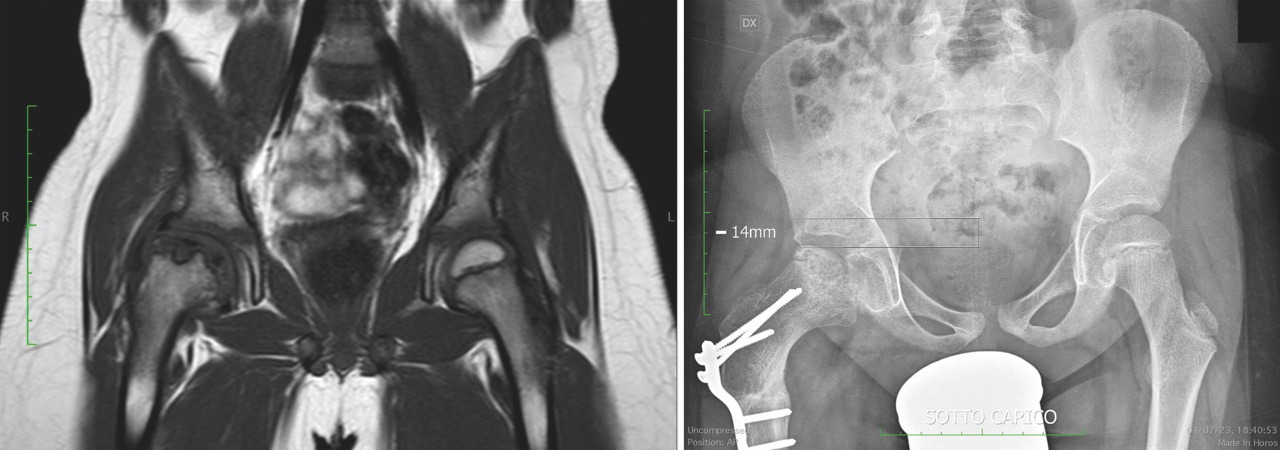

La radiografia tradizionale è la metodica di riferimento e permette di calcolare determinati parametri in modo da definire non solo il grado di displasia ma anche il trattamento ottimale. Le proiezioni indicate sono la antero-posteriore (AP), AP con arto in abduzione per verificare il mantenimento(miglioramento della congruenza articolare, la falso profilo di Lequesne, la proiezione di Dunn. Nei casi più complicati è di aiuto una pianificazione con TC e lo studio di eventuali patologie intrarticolari associate con RM (lesioni condrali, lesioni del labbro e impingement femoro-acetabolare).

Vista l’ampia varietà della displasia, spesso non si riesce a trattarla con la sola PAO, per cui è necessario associare anche una PFO. L’indicazione varia in base al reperto radiografico nelle proiezioni funzionali dell’anca (abduzione, flessione e intrarotazione).

Partendo dalla RX antero-posteriore possiamo valutare il deficit di copertura acetabolare e lo spazio articolare, per poi passare alle proiezioni funzionali.